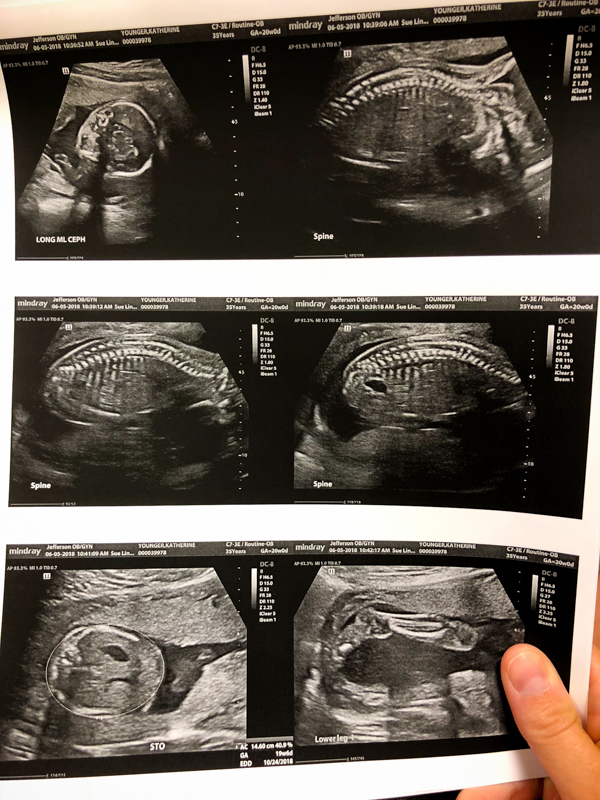

Both Thomas and I were nervous going into the appointment because they scan all the baby’s major organs and look for anything abnormal. We both let out a huge breath we’d been holding when it looked like everything was healthy. I’m a lot more anxious about things going wrong this time around, and I’m well aware that even if they baby is born healthy, the worry never ends.

Baby B (which stands for Baby Brother, Baby Boy, Baby B versus Baby A) was wiggling around a lot in there. He was in a pike position with his hands shooting out in front of him nearly touching his toes! We weren’t able to get a good profile pic, but look at this leg!

Some more body pics – he’s measuring nearly 3/4 of a pound in weight. Ultrasounds are crazy!